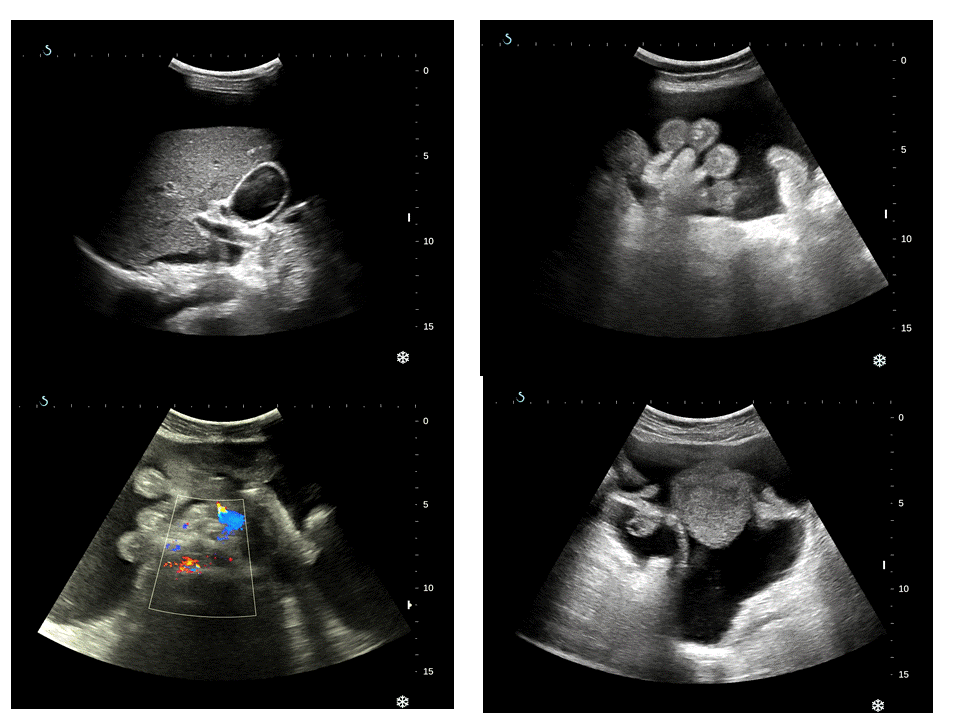

Woman 30 yo with total colectomy by colon poliposis for 2 years ; one month ago she detected ascitesunknown origineat MEDIC [19, April]. Ultrasound showed that high volume ascites,normal liver and.kidney(see 4 pictures ultrasound).